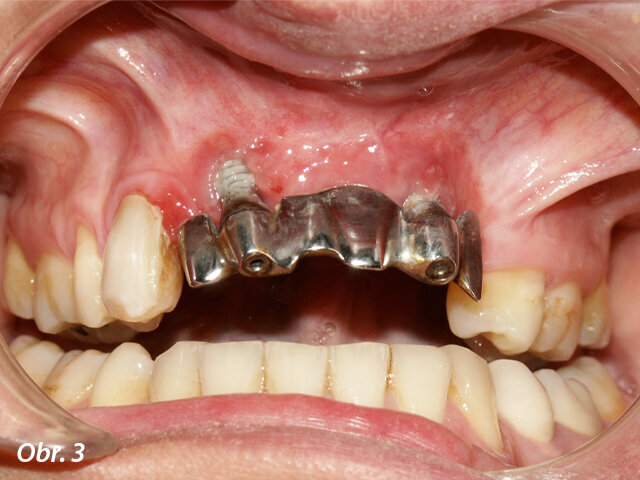

Po sejmutí zubní náhrady a provedení vyšetření byla u implantátů stanovena extrémně negativní prognóza (obr. 3), což je u náhrad tohoto typu v horní čelisti časté. Pravý implantát vykazoval ztrátu většiny vestibulární kosti, která způsobila značnou recesi sliznice. Tkáně byly hyperplastické a ztěžovaly hygienu. Konstrukce náhrady byla mimo středovou linii nejspíše kvůli implantátům, což vysvětlovalo i umístění protetických zubů mimo středovou osu.

Vyšetření po třech letech: negativní krátkodobá prognóza implantátů v důsledku výrazné recese u pravého implantátu a hyperplastických tkání.